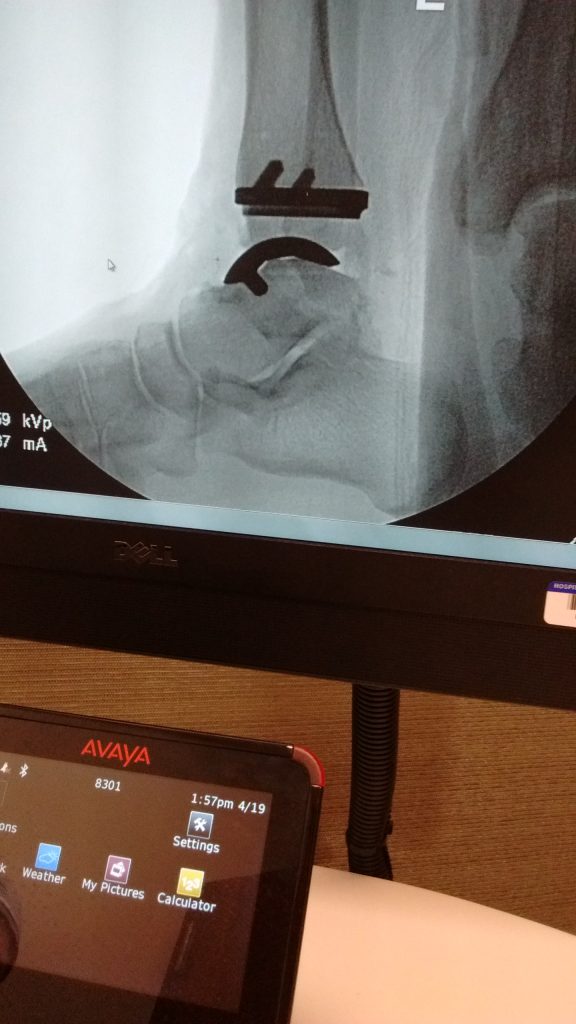

Ankle Replacement (Ankle Arthroplasty)

HSS and Dr. Deland's expertise and care have given me my life back! Degenerative arthritis of my ankles had slowly destroyed my active life style over the past 20 years, taking way running, skiing, biking, and by 2014, threatened to stop me from walking more than a short distance without suffering real pain. I chose not to let that happen and found in Dr. Deland one of the few surgeons in the world capable of successfully doing my complicated operation. Did I mention that I had just turned 80 and have a fused left ankle or that the degree of tilt in my right ankle was over 25 degrees?

After considerable examination and consultation with his team of associates, Dr. Deland gave me a 75% chance of success. My options were threefold: (1) Fuse the right ankle and face a lifetime of "Frankenstein-style" walking for short distances; (2) Amputate my right leg below the knee and learn to wear a prosthesis; or (3) Attempt the total ankle replacement. I chose # 3.